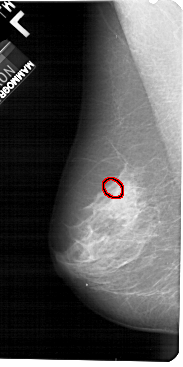

FILE: A_1316_1.LEFT_MLO.OVERLAY

TOTAL_ABNORMALITIES 1

ABNORMALITY 1

LESION_TYPE CALCIFICATION TYPE PLEOMORPHIC DISTRIBUTION CLUSTERED

ASSESSMENT 4

SUBTLETY 3

PATHOLOGY BENIGN

TOTAL_OUTLINES 1

BOUNDARY